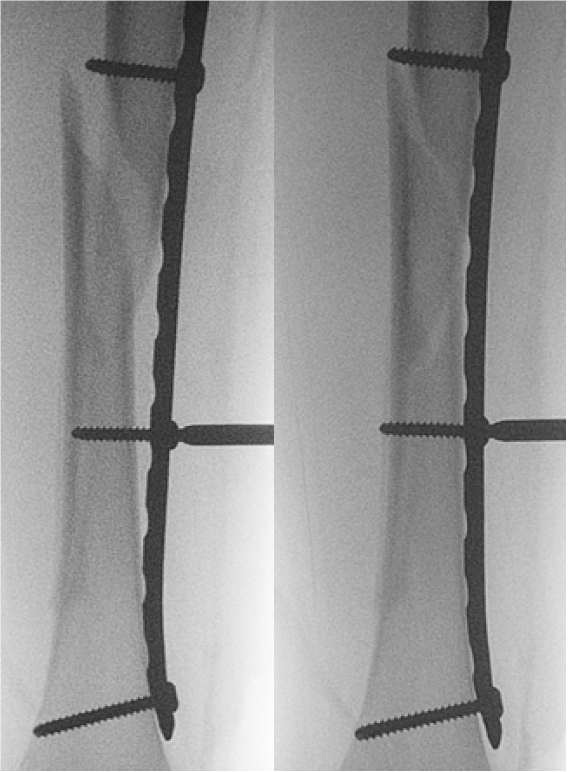

Plate

Indication

- length unstable fractures (spiral / comminuted)

- very distal or proximal fractures

- patient inability to non weight bear (cognitive impairment / developmental delay)

Options

1. Open Plating

2. Submuscular bridge plating

Technique

- supine on radiolucent table or traction table

- incision 5cm proximal or distal (depending # site)

- blunt dissection to periosteal layer

- run bristow or cobb elevator submuscularly

- 3.5 or 4.5mm LCP plate (depending on patient size and age)

- place plate submuscularly

- use stab incisions to place 3 screws above /below fracture

- sufficient spread

Postop

- TWB / PWB for 6/52 until union

- removal at 6/12

Results

Abott et al. J Paediatr Orthop 2013

- comparison of open v submuscular bridge plating in 79 patients

- increased blood loss in open plating

- increased rotational asymmetry in bridge plating

- no other difference between two groups

https://pubmed.ncbi.nlm.nih.gov/23752149/